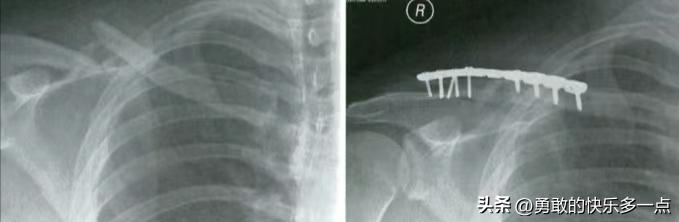

锁骨骨折钢板内固定图片